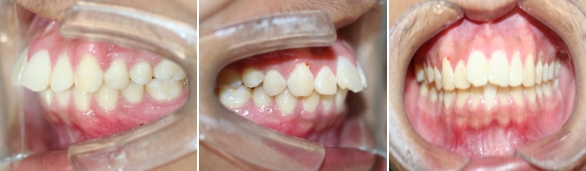

口内检查 :上下牙弓均为卵圆形 左右基本对称 上颌牙弓轻度拥挤 下颌缺失一颗下切牙

左右侧磨牙均为一类咬合关系,前牙深覆合、深覆盖。

临床 前牙深覆合,深覆盖,后牙中性关系

上下前牙唇倾

双唇前突

治疗预计效果和实际效果

治疗后

治疗前后对比